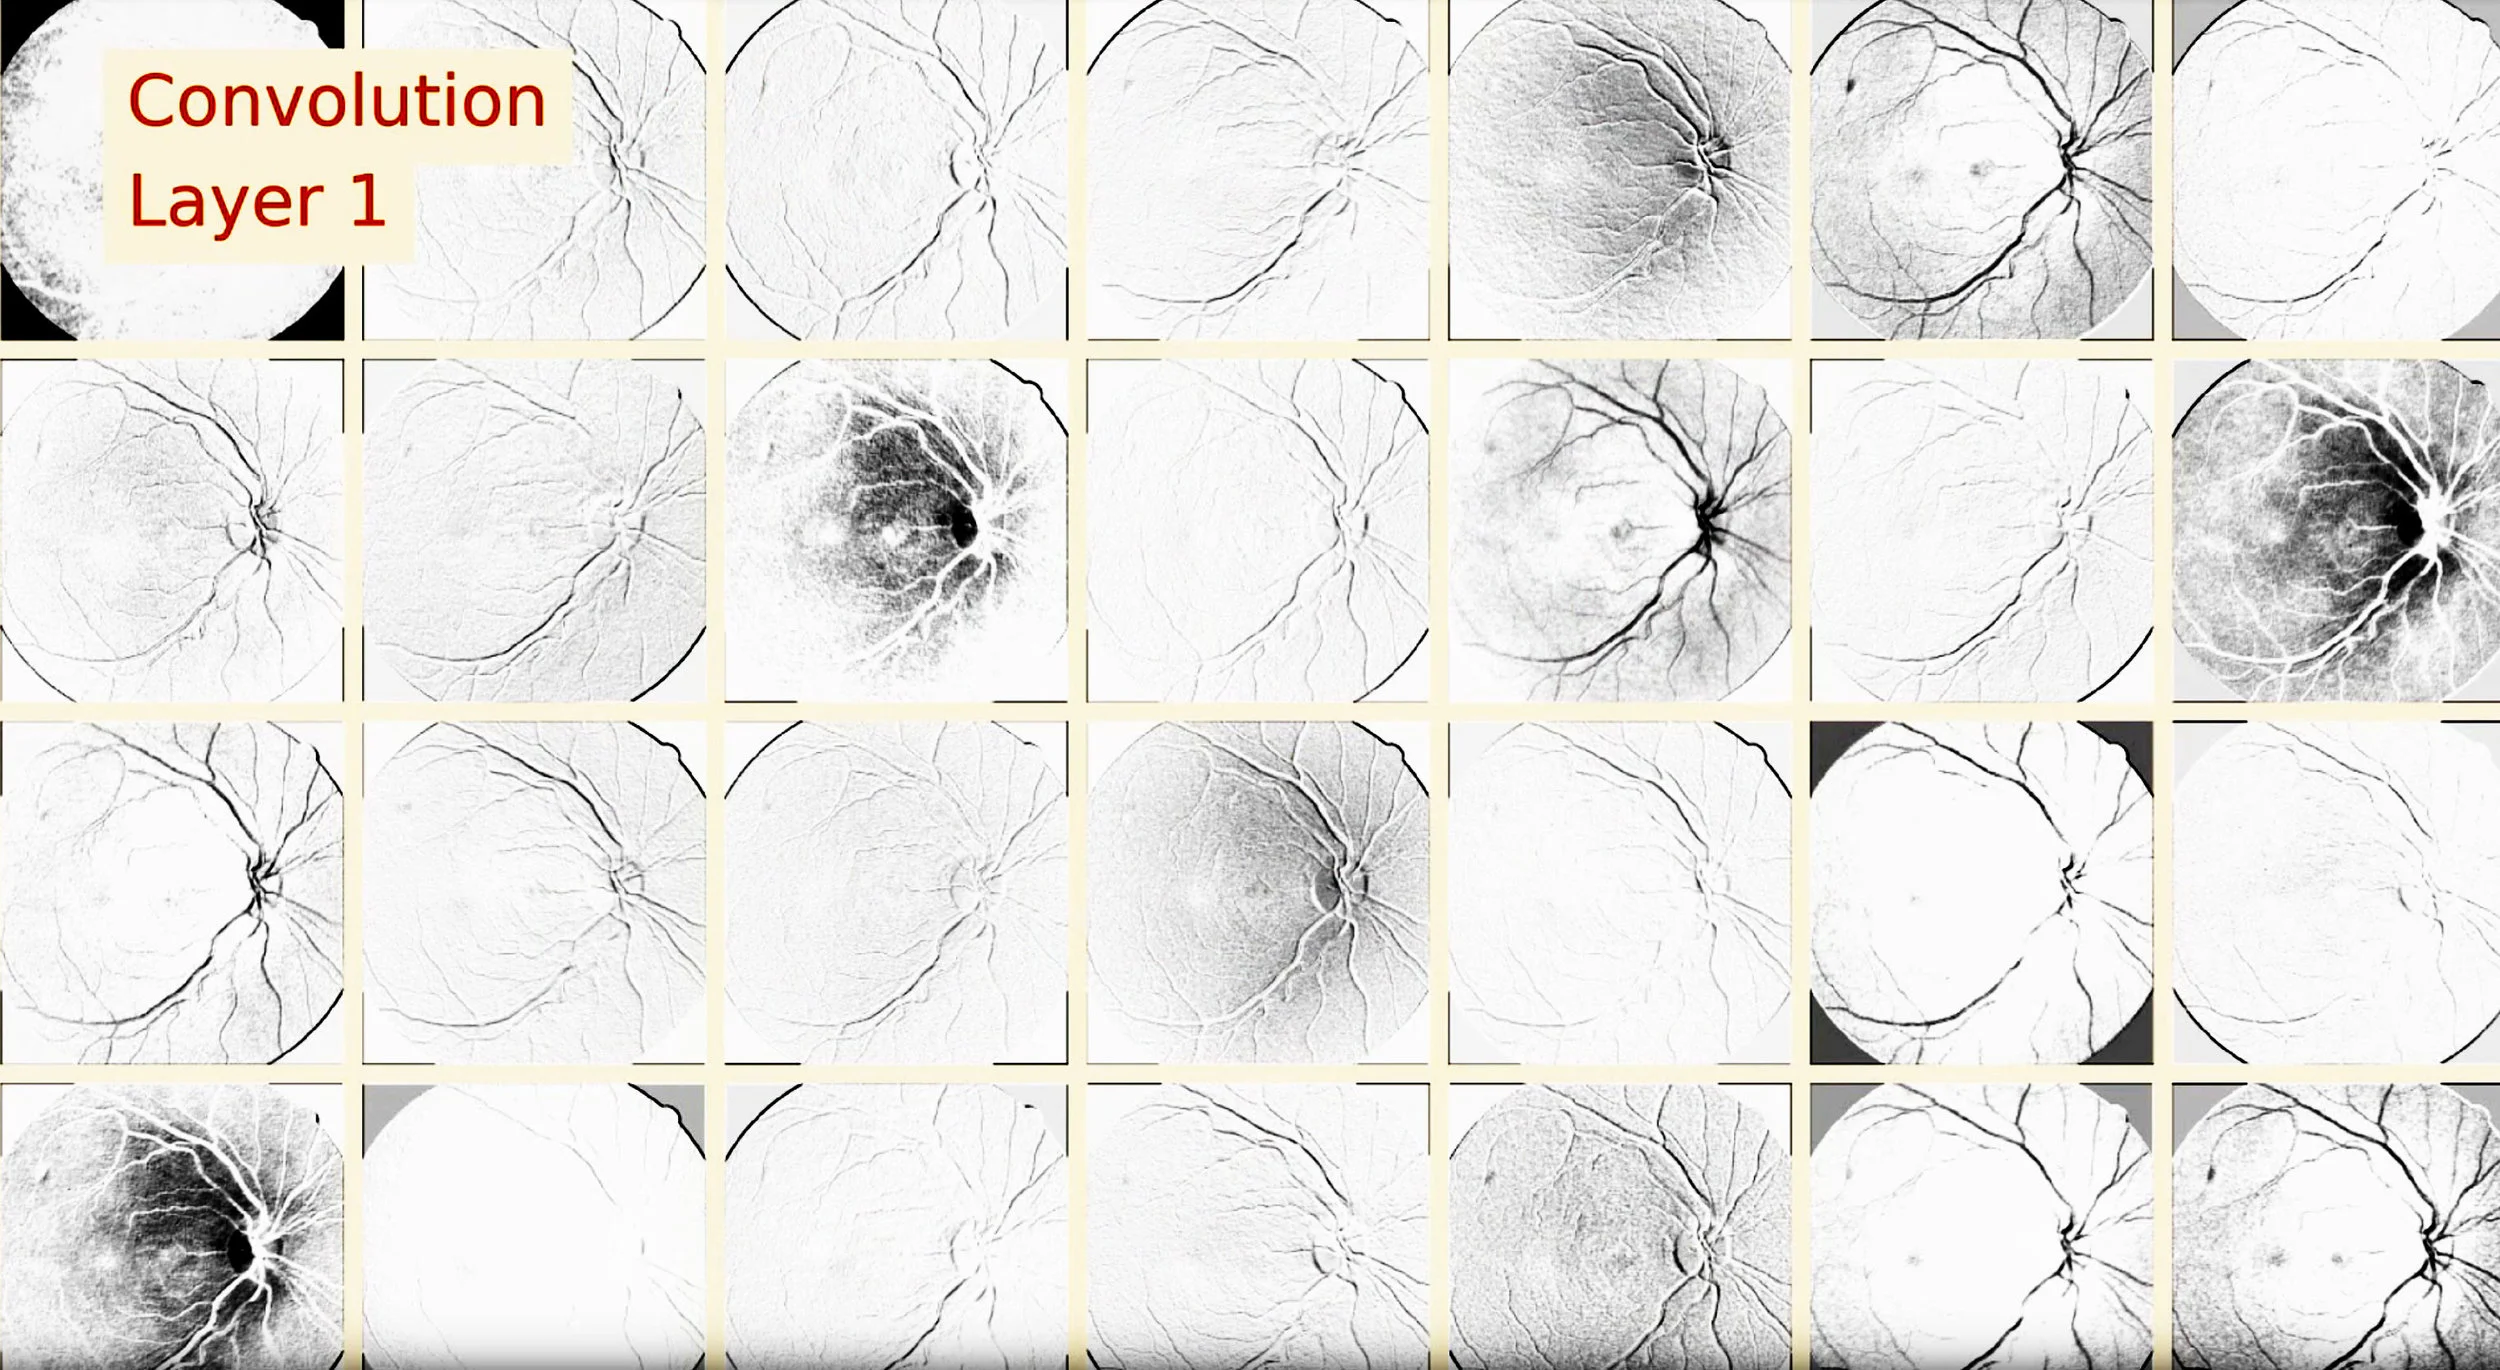

We use VGG style convolutional neural networks trained with "Lasagne" and "nolearn" with large color images, various types of data augmentation, dynamic resampling for class imbalance and a "per patient'" feature blending strategy which takes advantage of having pairs of sample images for each patient at our disposal. The final solution is a simple average of blends with features from two deep convolutional networks and three sets of weights for each network.